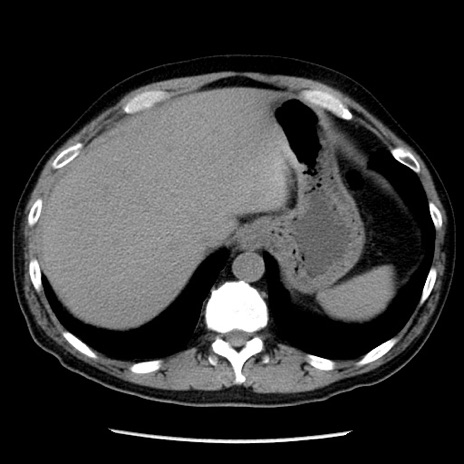

症例29(横断像)

【症例】40歳代男性

【現病歴】2日前から胃痛あり。徐々に周期的な激痛に変化した。本日になっても激痛があるため受診。

【身体所見】意識清明、BT 38-39℃台あり、腹部:膨満、やや硬、右下腹部に圧痛あり。

【データ】WBC 8500、CRP 23.26